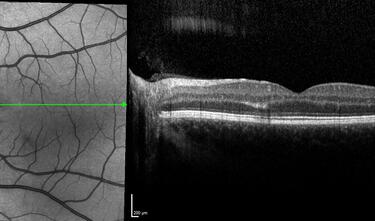

Clase 1 - Conceptos esenciales en fisiología y anatomía de la retina

Clase 15 - Depósitos y signos específicos en DMAE no neovascular

Clase 18 - Signos estructurales diferenciales entre neurodegeneración y exudación en DMAE